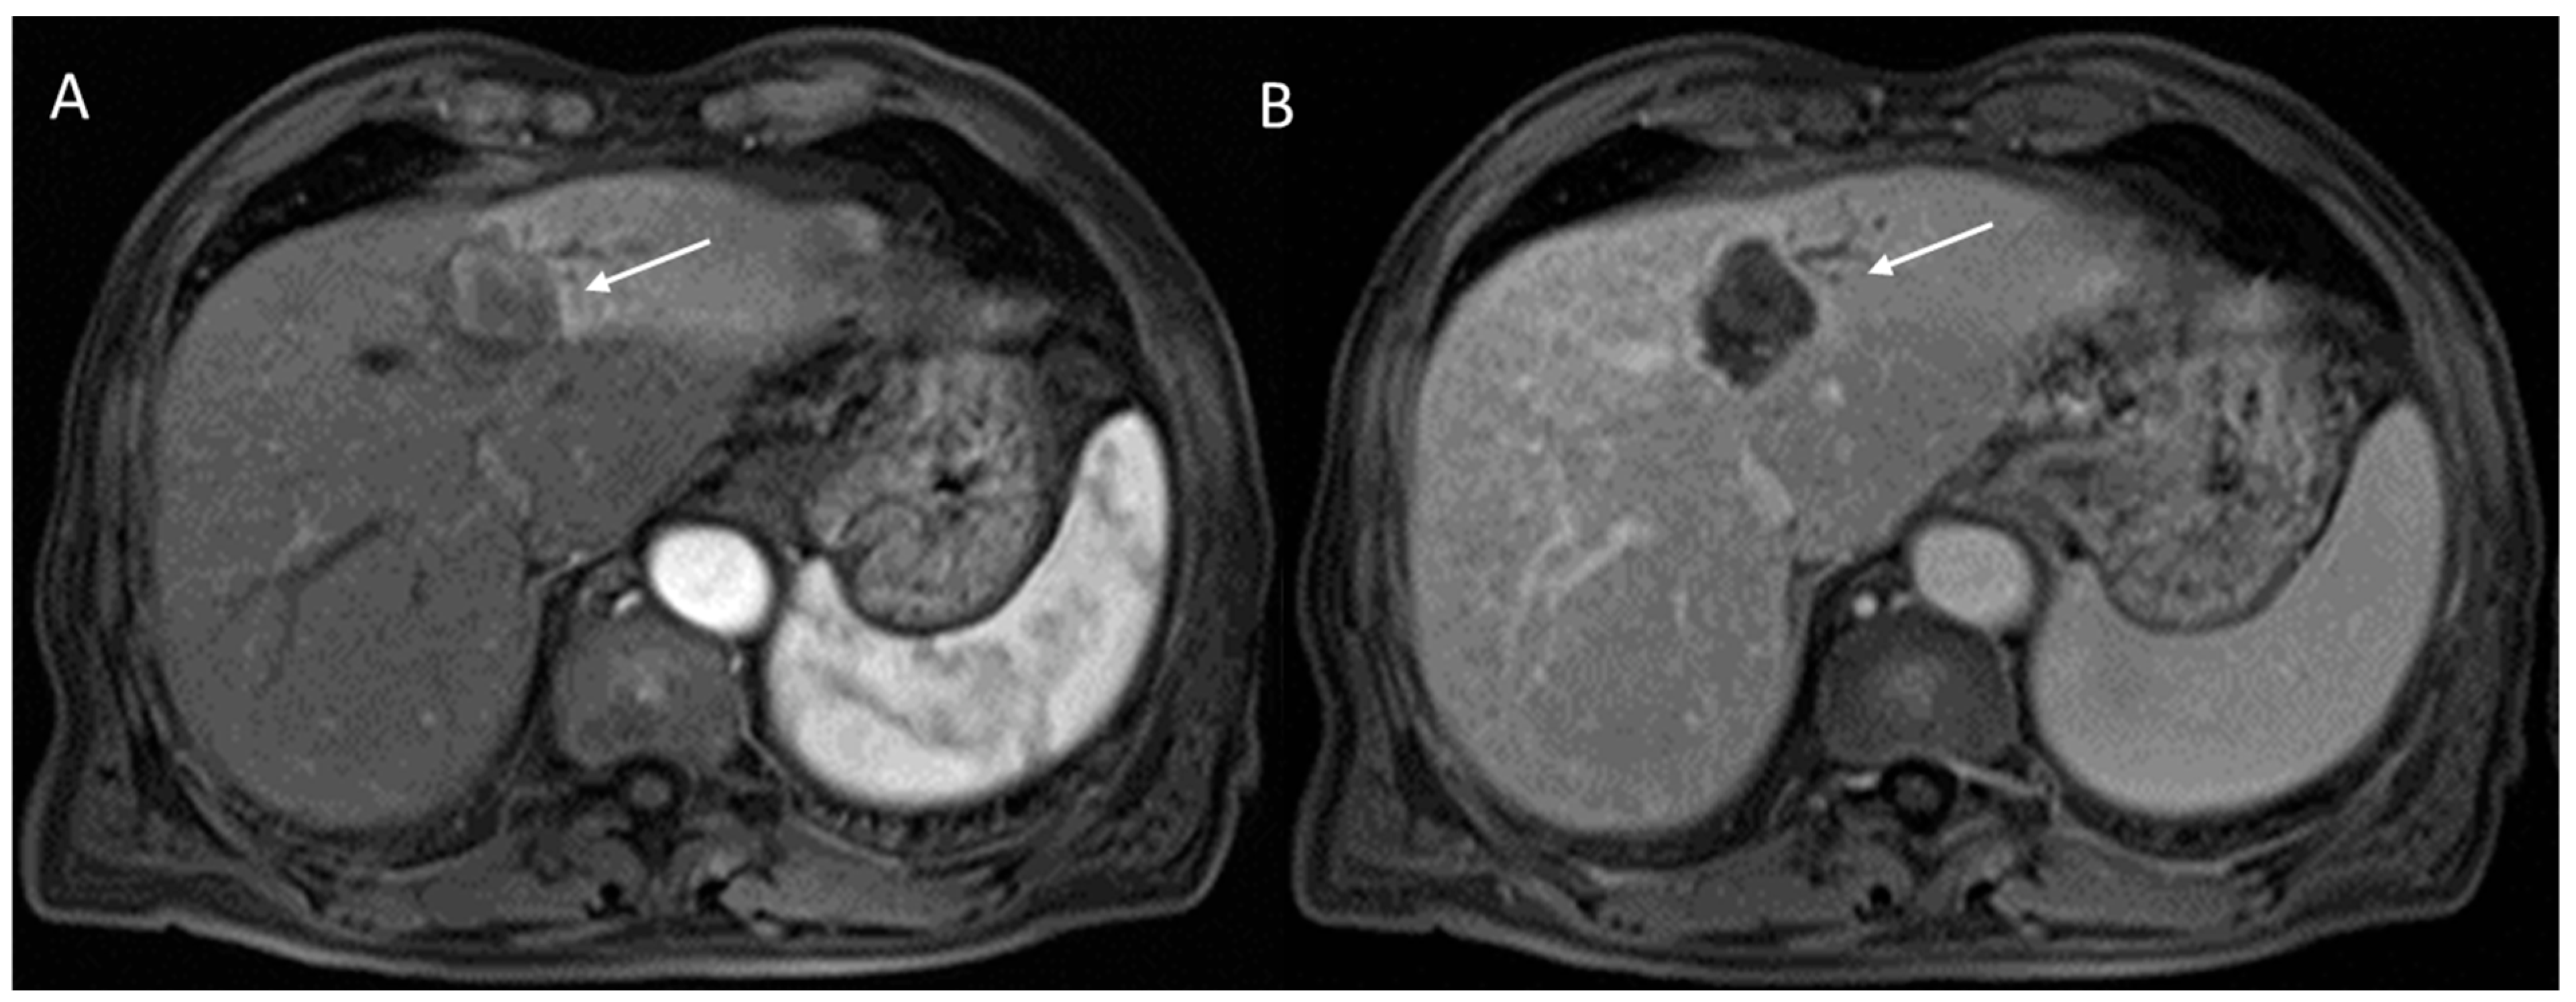

2.2.5. LR-M Category

2.3. CEUS-LI-RADS